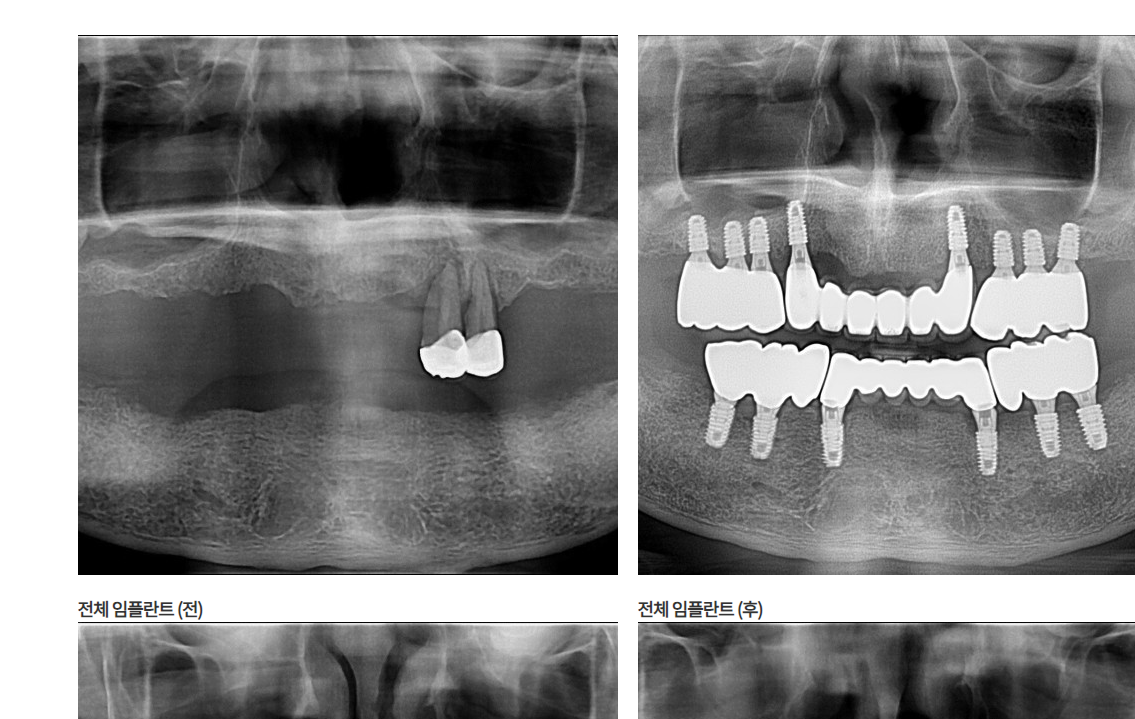

- 진료 과목: 원데이 임플란트, 네비게이션 전악 임플란트, 고난이도 뼈이식, 심미보철, 투명 교정, 코골이 치료, 턱관절 치료, 충치 및 신경 치료 등 다양한 진료 서비스 안내.

- 임플란트 전문: 환자의 상태에 맞춘 정밀한 진단과 시술로 자연스러운 결과를 제공합니다.

- 최신 기술 도입: 디지털 임플란트 시스템과 정밀 CT 촬영을 통한 체계적인 진료.

- 경험 많은 의료진: 다양한 임플란트 케이스를 성공적으로 시술한 경력을 보유.